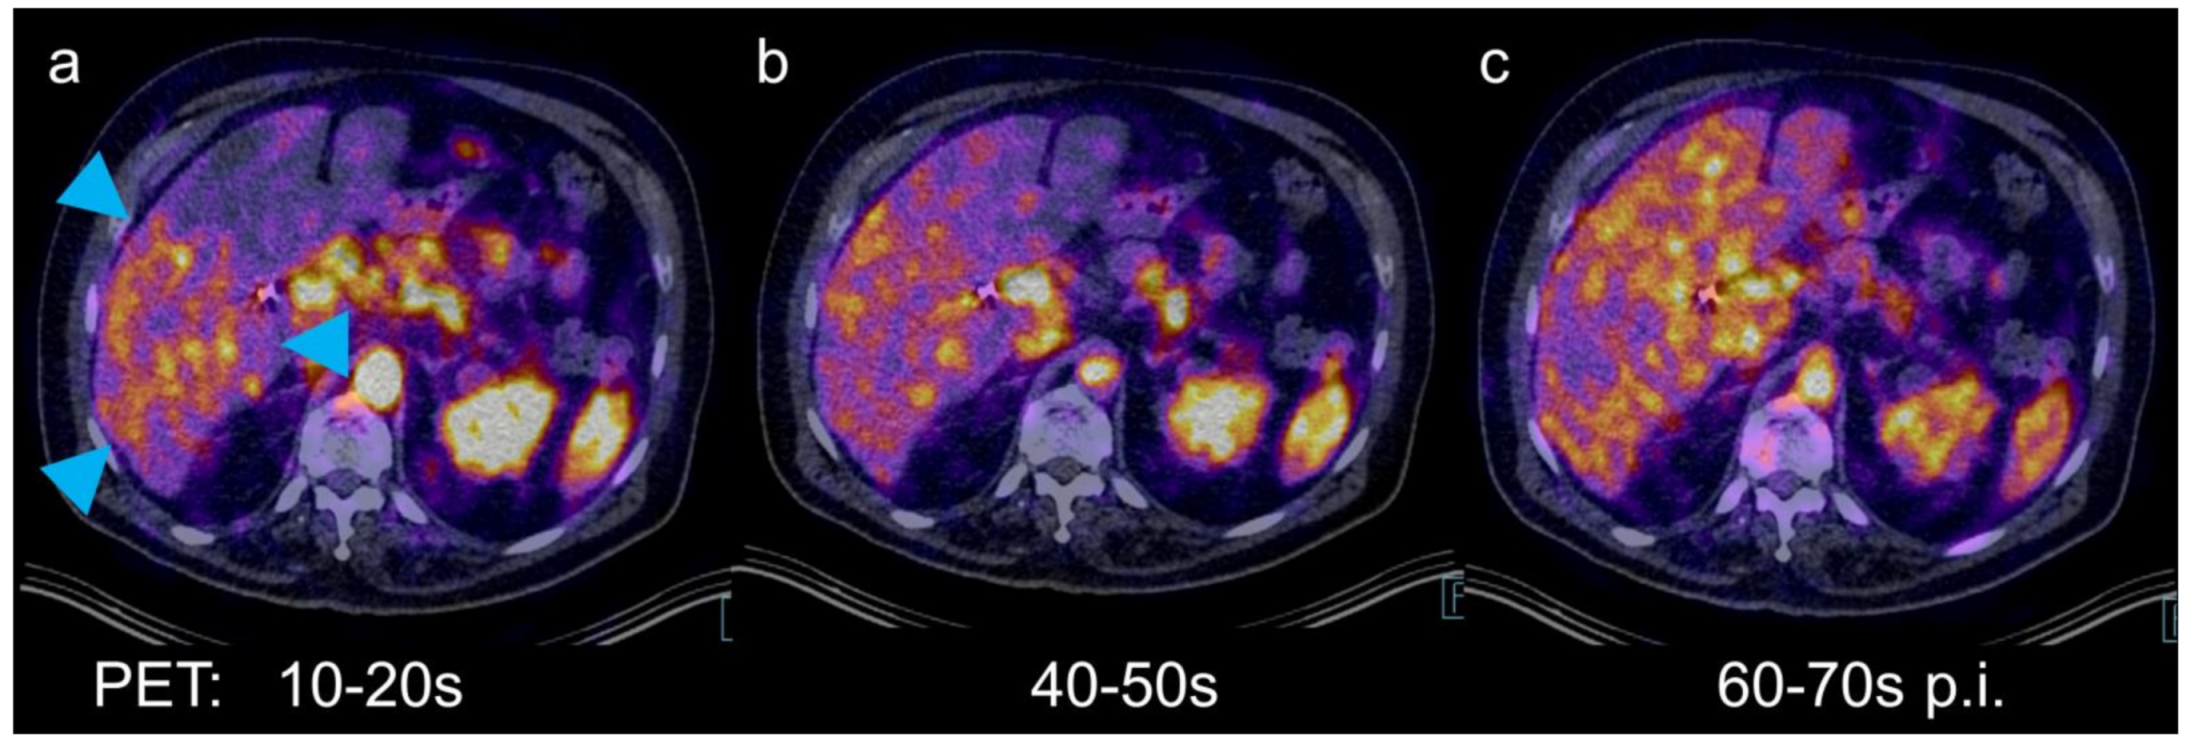

Dynamic PET/CT with the Hepatobiliary Tracer [68Ga]Ga-Tmos-DAZA for Characterization of a Hepatic Tumor

Freesmeyer, M.; Greiser, J.; Winkens, T.; Gühne, F.; Kühnel, C.; Rauchfuß, F.; Tautenhahn, H.-M.; Drescher, R. Dynamic PET/CT with the Hepatobiliary Tracer [68Ga]Ga-Tmos-DAZA for Characterization of a Hepatic Tumor. Diagnostics 2021, 11, 660. https://doi.org/10.3390/diagnostics11040660